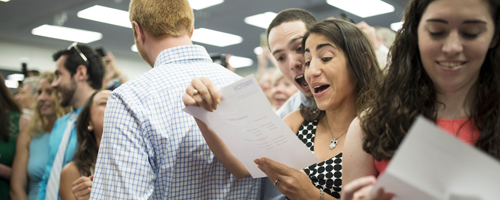

Today, the members of the Charles E. Schmidt College of Medicine Class of 2019 joined thousands of medical students across the nation to celebrate Match Day. Surrounded by family, friends, and faculty mentors, the students ripped open sealed envelopes to find out where they ...

Today, the Charles E. Schmidt College of Medicine celebrated Match Day, an important rite of passage for medical students nationwide. High-fives, hugs and happy tears filled the room as the Class of 2018 ripped open their envelopes to reveal where they will spend the next fe...

Today, the Charles E. Schmidt College of Medicine Class of 2017 celebrated one of the most exciting events of the year: Match Day. During this annual rite of passage, medical students find out where they will spend the next few years of medical training as residents.Th...

Friday I had the pleasure of participating in what has become one of my favorite events of the year, Match Day for our Schmidt College of Medicine. Match Day is the national program that pairs new physicians with hospital-based residency programs and takes place at the same ...